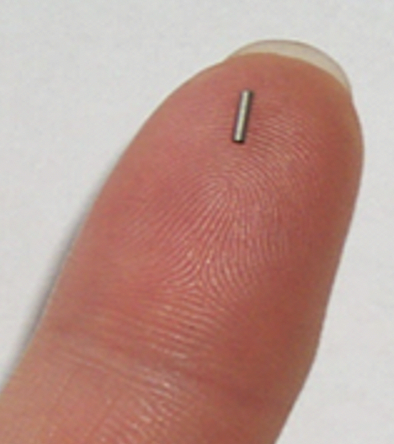

其实啊,是医生将带有放射性的碘125粒子通过一系列操作,植入到病人身上的肿瘤中去,在肿瘤内组织内部对肿瘤进行照射,从而达到治疗目的,属于近距离放射治疗的范畴。

(真实图,非常小巧的粒子)